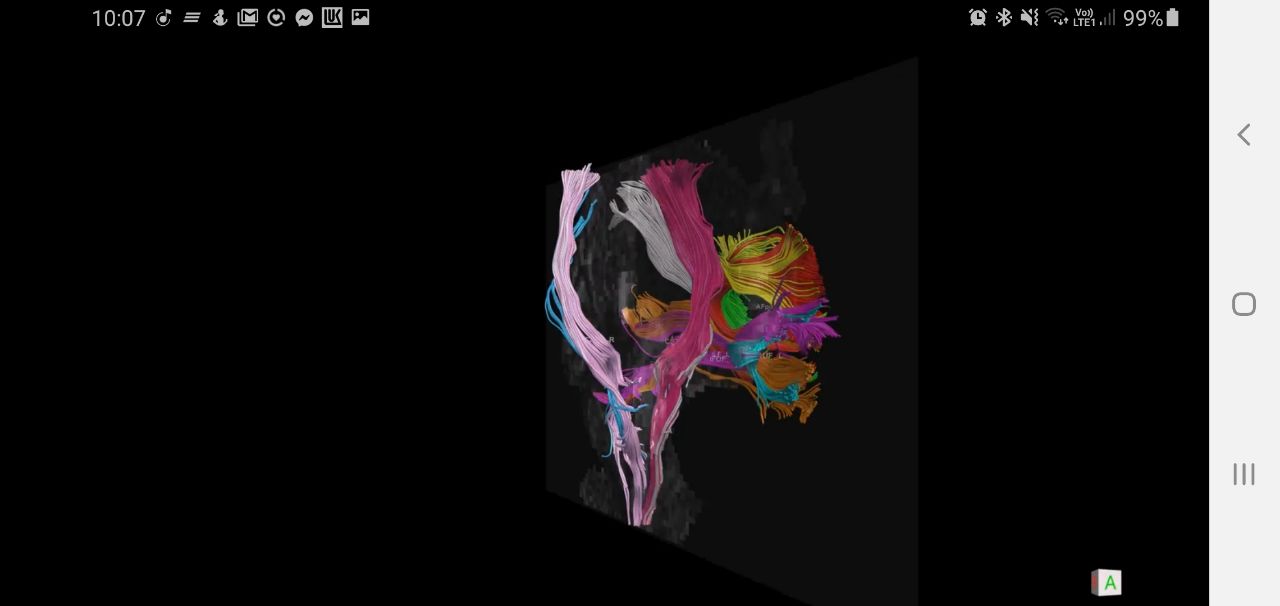

Чуть больше месяца назад в отделение поступила девушка 33 лет с жалобами на периодическую головную боль и однократный эпизод утраты сознания. При МРТ головного мозга выявлена большая опухоль обеих лобных долей с поражением мозолистого тела, размером 11,1х6,5х7,5см. (объем 283,3см3). Основной массив опухоли локализовался в левой лобной доле, подходя вплотную к зонам на коре, отвечающим за движения в правых конечностях и за произношение слов. В глубине опухоль находилась в непосредственной близости от речевых трактов и пирамидных трактов с двух сторон. Повреждение их могло привести к нарушениям речи или парализации пациентки. Мозолистое тело (структура, которая соединяет два полушария мозга между собой) было поражено опухолью на 75%. Разобщение полушарий (пересечение мозолистого тела) может привести к выраженным психическим нарушениям. В структуре опухоли проходили крупные сосуды, питающие до 30% полушарий. Все это делало предстоящую операцию действительно сложной. Так же напрягало еще то, что больную кроме умеренной головной боли ничего больше не беспокоило.

Обсудив все риски с пациенткой и ее родственниками мы выполнили операцию. Т.к. опухоль локализовалась вблизи речевых зон и трактов, операцию выполняли с пробуждением и общением с пациенткой во время удаления опухоли. Стимулируя каждый миллиметр коры и белого вещества головного мозга, мы выявили все функциональные (речевые и двигательные зоны и тракты, их соединяющие) зоны. Во время операции больная активно общалась с нашими помощниками нейролингвистами - Andrey Zyryanov и Гордеевой Елизаветой из команды Olga Dragoy. Сохранность важных мозговых структур отслеживала наш нейрофизиолог Мария Подгурская. Благодаря их помощи нам удалось удалить почти всю опухоль из обоих полушарий и мозолистого тела. Это заняло у нас 7 часов. Операционная бригада, помимо указанных специалистов, состояла из Ольга Вобликова, Алексей Димерцев, Кристина Ключникова, Алексей Корябочкин.

Сразу после операции больная меня напугала - она не могла говорить и у нее развилась выраженная слабость в правых конечностях. Из имеющихся данных МРТ после операции мы быстро построили тракты. Оказалось, что все они сохранны (и речевые, и двигательные). Это успокоило и мы решили проводить консервативную терапию и ждать. Т.к. при удалении опухоли были резецированы премоторная кора, область лобного косого тракта, больной было трудно начать движение или начать говорить. К тому же полушария между собой связывались только через 25% мозолистого тела, что замедляло восстановление.